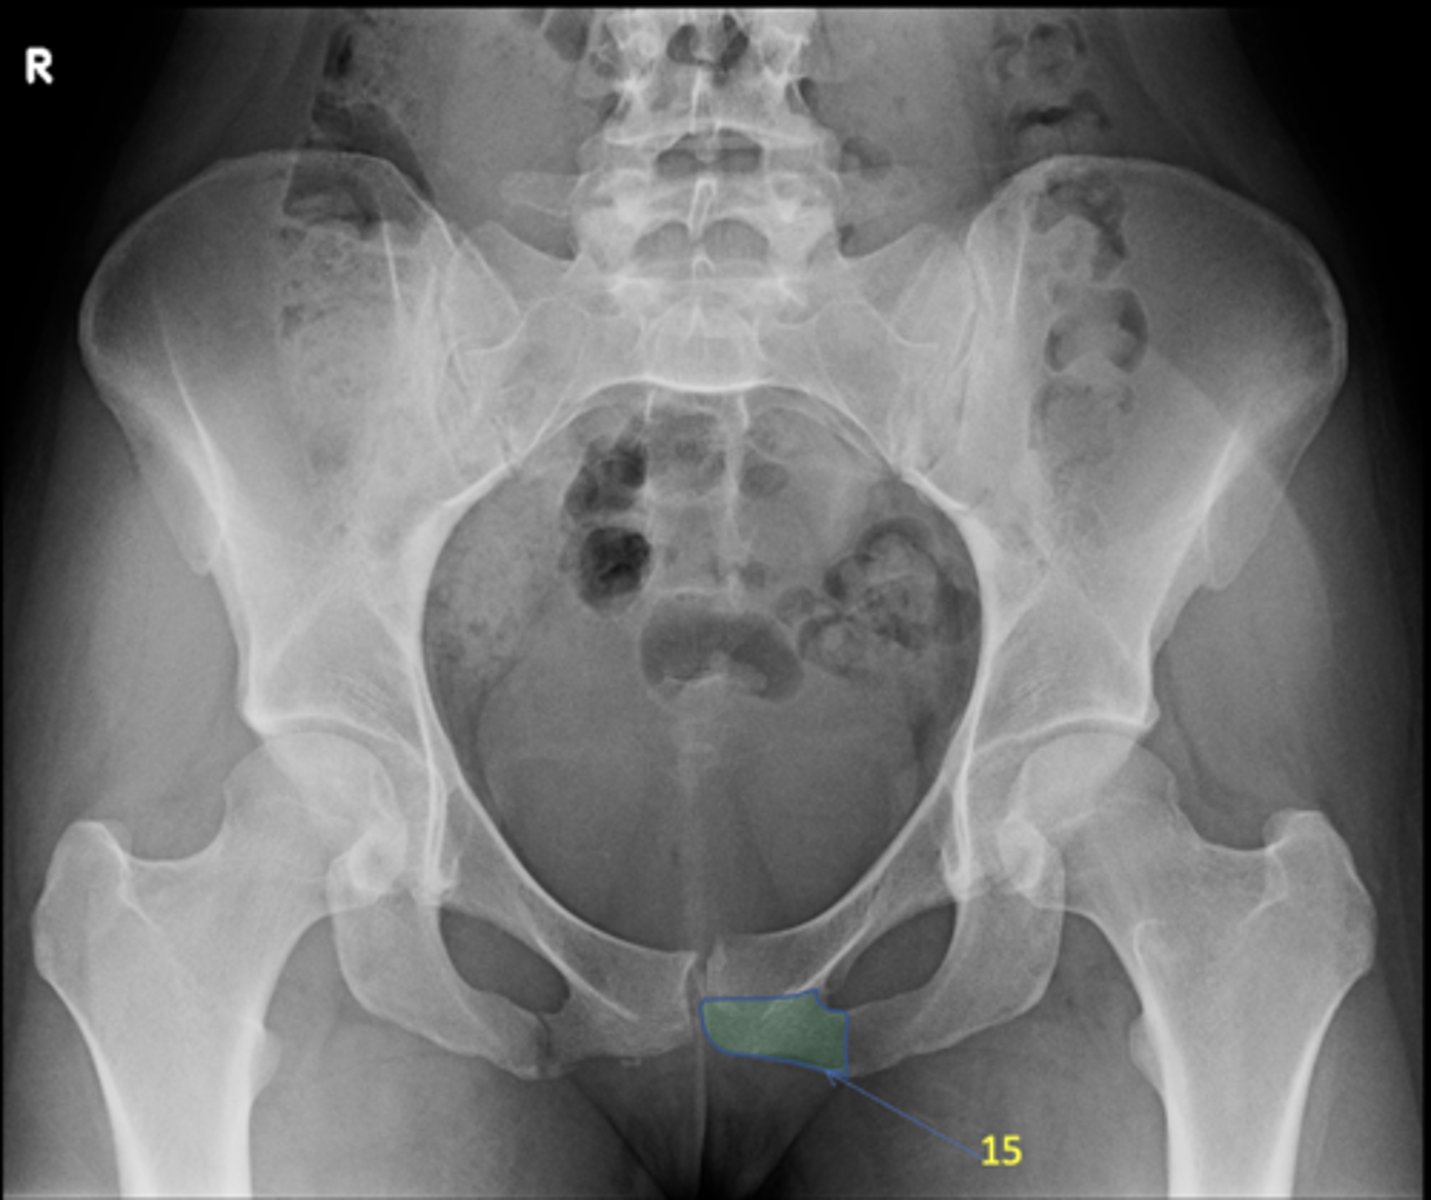

AP pelvis

View?

Right lesser trochanter

ID 2

Left greater trochanter

ID 3

Right iliac crest

ID 4

Right iliac fossa

ID 5

Left anterior superior iliac spine

ID 6

Right ischium

ID 7

Left ischial spine

ID 8

Right fovea capitis

ID 9

Left obturator foramen

ID 10

Right posterior superior iliac spine

ID 11

Left femoral neck

ID 12

Left anterior inferior iliac spine

ID 13

Left inferior pubic ramus

ID 15

S1 tubercle

ID 16

Left sacral ala

ID 17

Right femoral head

ID 19

Kohler's teardrop

ID 20

Right pubis

ID 21

Right anterior sacroiliac joint

ID 22 (joint)

Left superior pubic ramus

ID 24

Right acetabulum

ID 25

Right intertrochanteric crest

ID 26

Left ilium

ID 27

Right ischial tuberosity

ID 28

Bladder

ID 29

Ascending colon

ID 30